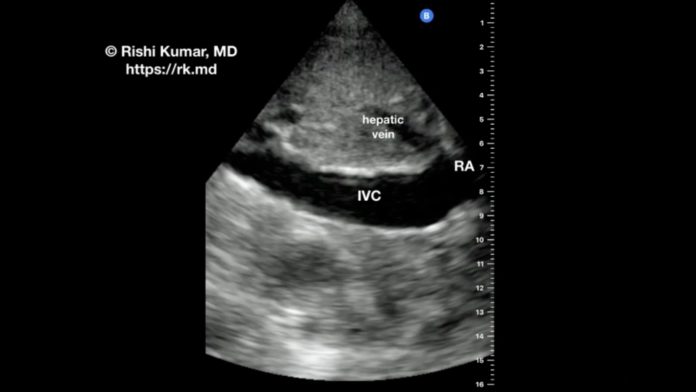

POCUS – IVC Versus Aorta

The subcostal view of the inferior vena cava (IVC) is used to assess IVC diameter and respirophasic variation to gauge “volume status.” However, in my clinical practice, I find this technique fairly useless outside of the extremes. For example, an IVC diameter of 28 mm makes me less inclined to give volume and more concerned about right-heart dysfunction, hypervolemia leading to venous congestion, etc.

I obtain this view by palpating the xiphoid process, moving just inferior to it, and aiming my ultrasound probe straight down to the spine with the probe indicator facing the patient’s head.

The superior and inferior vena cavas are “right-sided” structures, whereas the thoracoabdominal aorta is a “left-sided” structure. Because the IVC and aorta both run longitudinally in this view, it’s important to distinguish one structure from the other. Panning the ultrasound beam rightward will reveal the IVC with the hepatic vein(s) draining into it as well as the IVC-right atrium (RA) junction. Panning the ultrasound beam leftward will reveal the thicker-walled aorta, which runs alongside the spine and does not show respiratory variation. Remember, pulsatility alone is unreliable (think about patients on mechanical circulatory support, severe tricuspid regurgitation, etc.)!

In this video, I pan back and forth between the IVC and descending aorta on my Butterfly iQ+ to show the subtle but important differences between these structures. I often use point-of-care ultrasound (POCUS) as a cardiothoracic anesthesiologist and intensivist in my OR and ICU practices.